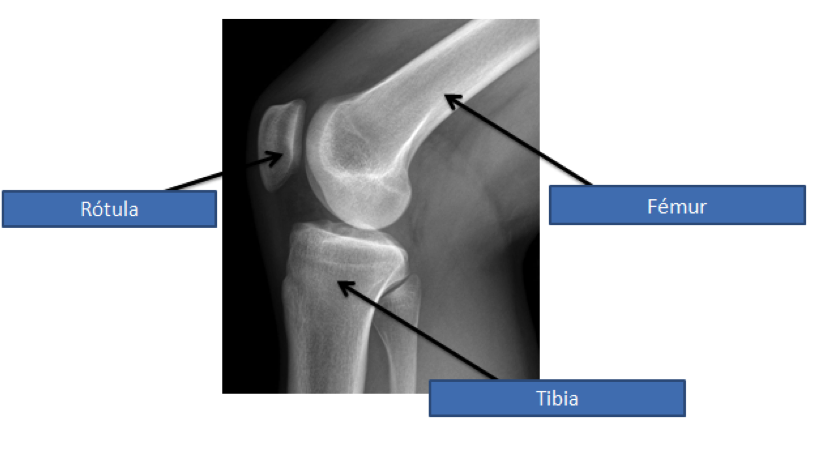

ANATOMÍA DE LA RODILLA

INTRODUCCIÓN La rodilla es la articulación central de los miembros inferiores del cuerpo y una de las más importantes que tenemos. Soporta todo nuestro peso y nos permite caminar gracias a los movimientos de extensión y flexión de las piernas. También nos proporciona la capacidad de despegue y recepción en los saltos. Para esta disección hemos elegido la rodilla de cerdo porque es la más parecida a la humana con la que podíamos trabajar. PROCEDIMIENTO 1. Visión externa de la rodilla Como podremos comprobar en la disección la rodilla está formada por tres huesos: el fémur, la rótula y la tibia.